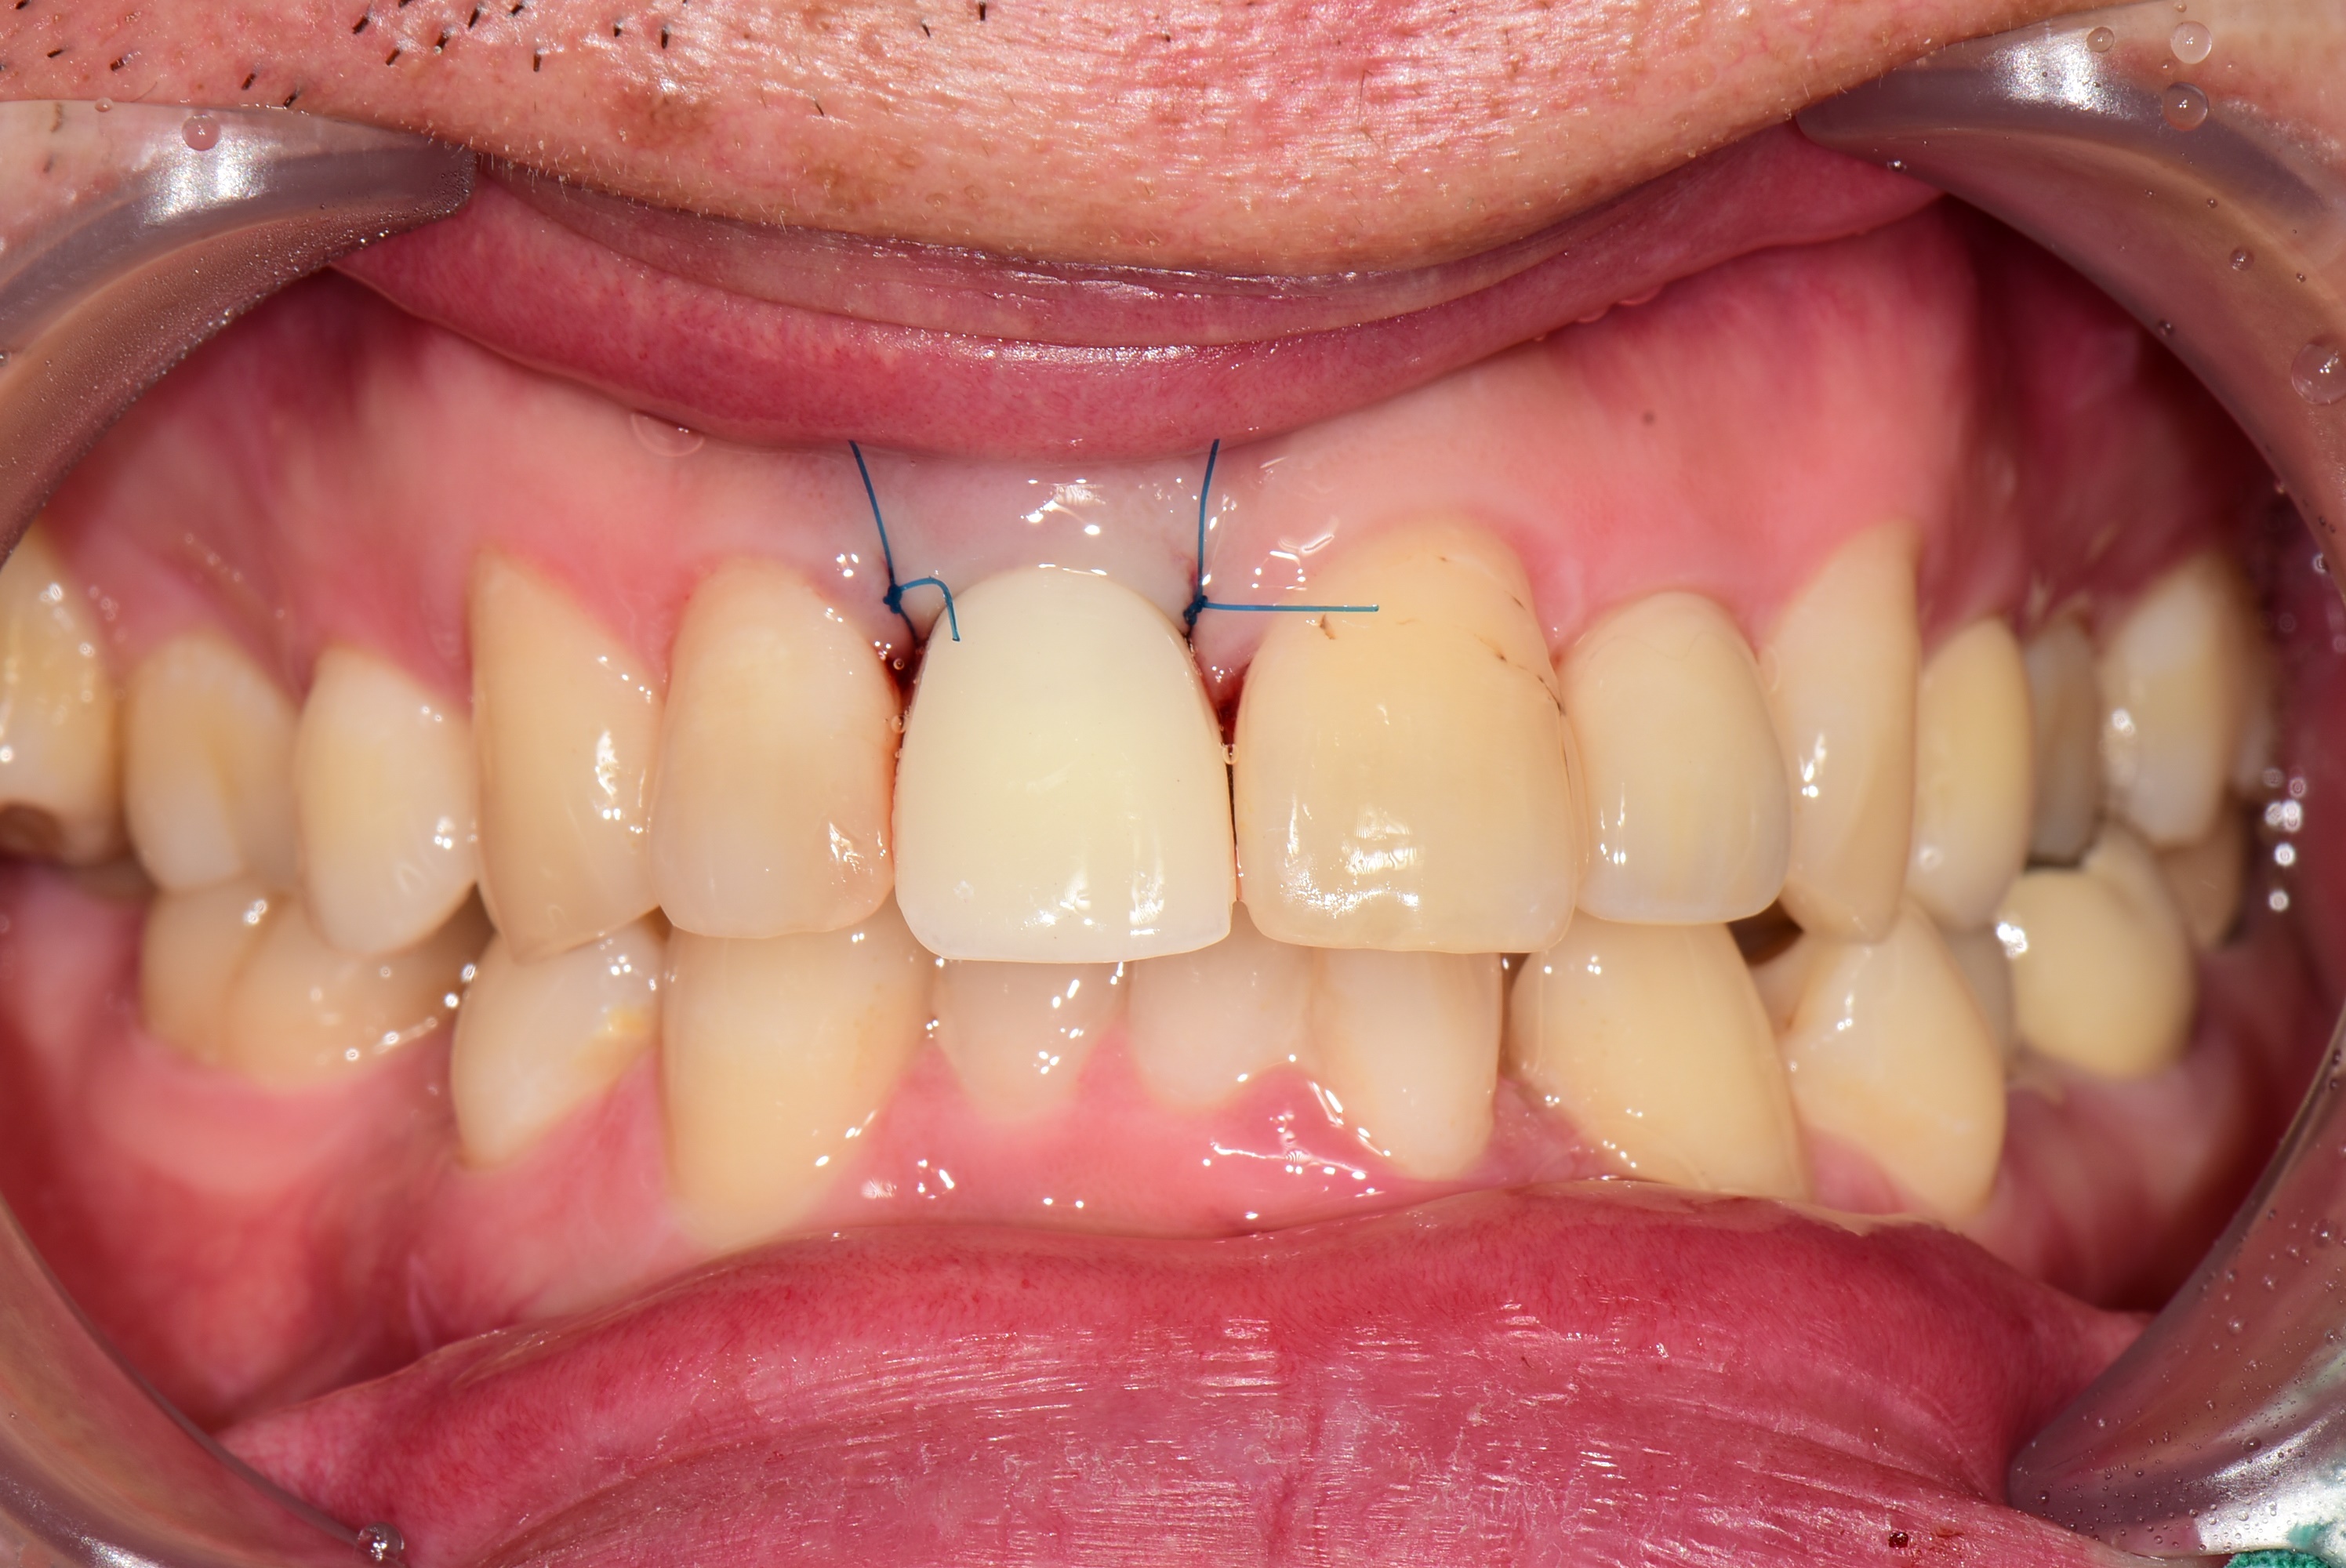

임플란트 식립후 임시치아를 바로 제작한 후 사진입니다.

아래는 3개월 후 최종 보철 후 사진입니다.